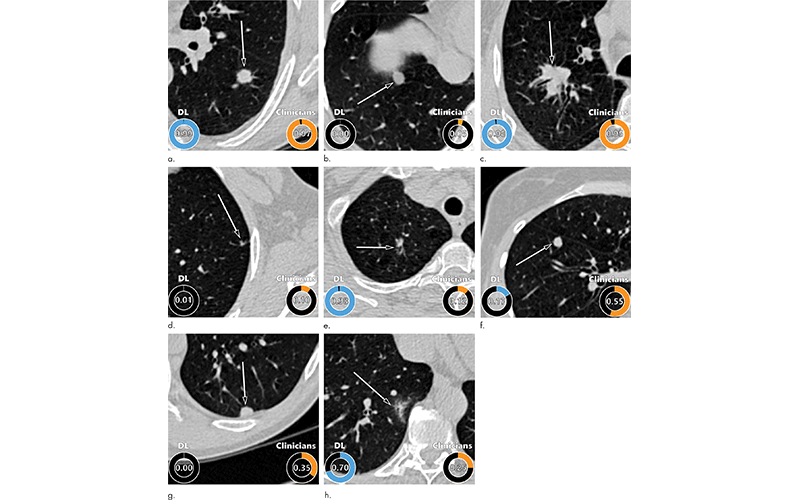

Examples of CT images in nodules from the Danish Lung Cancer Screening Trial (DLCST) with (a–d) high and (e–h) low agreement between the deep learning (DL) algorithm and the clinicians for malignancy risk estimation. Numbers in rings on bottom left of each image are the algorithm’s malignancy score, and numbers in rings on bottom right of each image are the clinicians’ median malignancy score. The extent of the color filling is proportional to the malignancy risk (on a scale of 0 to 1, where 0 represents the lowest risk and 1 represents the highest risk). (a) Image shows a 15-mm spiculated and lobulated malignant nodule (arrow) classified correctly by the DL algorithm and clinicians. (b) Image shows an 11-mm smooth benign nodule (arrow) classified correctly by the DL algorithm and clinicians. (c) Image shows a 29-mm benign lesion (arrow) suspected to be a malignant nodule by both the DL algorithm and clinicians. This participant was diagnosed with pneumonia at clinical workup. (d) Image shows a 5-mm malignant nodule (arrow) called benign by both the DL algorithm and clinicians. The growth of the nodule can be seen from follow-up CT examinations. (e) Image shows a 15-mm part-solid malignant nodule (arrow) classified correctly by the DL algorithm and not suspected to be malignant by seven of 11 clinicians. (f) Image shows an 8-mm benign nodule (arrow) predicted to be moderately suspicious by the clinicians and called benign by the DL algorithm. (g) Image shows an 11-mm malignant nodule (arrow) predicted to be moderately suspicious by most clinicians but called benign by the DL algorithm. (h) Image shows a 16-mm benign lesion (arrow) classified correctly by the clinicians and predicted to be highly suspicious by the DL algorithm.